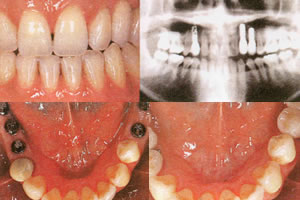

インプラント

一般的に歯科でインプラントといえば、人工歯根を意味しています。人工歯根とはいえ、歯槽骨内でしっかり固定されるところから「第2の永久歯」とも呼ばれています。

処置は歯が抜けたところに、金属などの土台を入れ、その上に義歯を取り付けて固定するもの。歯ぐきのドテが低くて、義歯が合わない人や、ブリッジなどで健康な歯を削るのがいや、という人に向いています。また一本から総義歯まで、どのような治療も可能で、残った歯に負担をかけないのも特徴です。